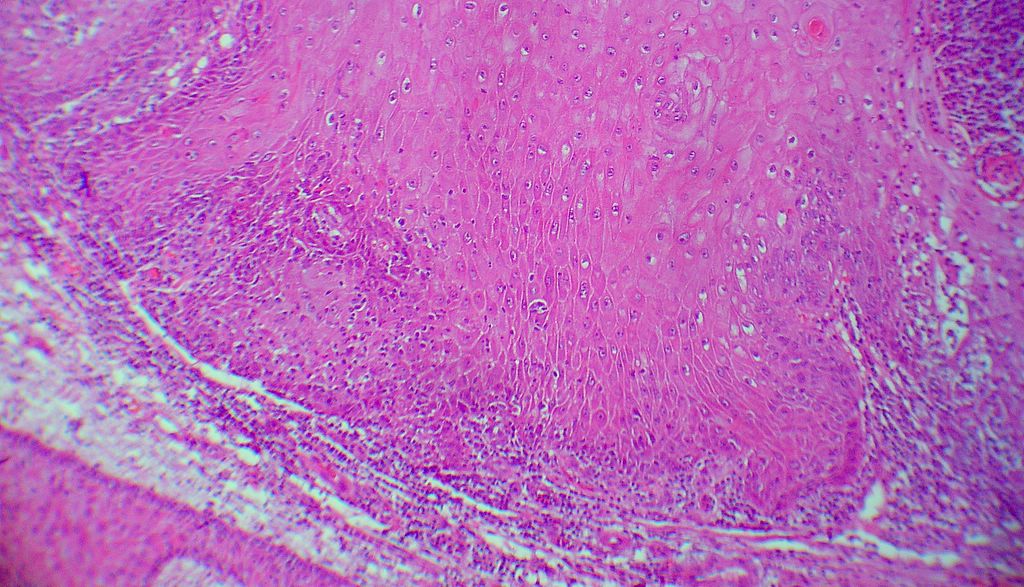

Biopsia (17553) que muestra los cambios que observas en las imágenes.

Descripción histológica

Diagnóstico